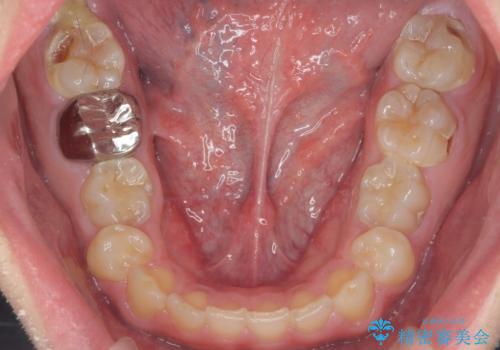

- 口の中を予算の範囲内でできるだけきれいにしたいとのことで来院された患者様です。

矯正治療と虫歯治療を組み合わせてご提案しましたが、ご予算との兼ね合いで虫歯治療のみを行うこととなりました。

奥歯は十分な歯の高さがなかったため、クラウンをかぶせる前に歯周外科治療で歯の高さを出しています。

歯科に通うようになってから磨き残しの状態も改善されていきました。